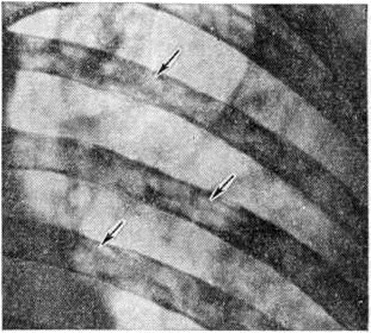

Множественно-очаговая форма встречается более чем в 70% случаев, рентгенологически характеризуется образованием множественных округлых дефектов диаметром до нескольких сантиметров. Изменения выявляются чаще всего в плоских костях (рисунок 9), реже — в длинных и коротких трубчатых. Каждый дефект чётко контурирован, реактивных изменений со стороны окружающей ткани при этом нет. В трубчатых костях корковое вещество изнутри истончается, костномозговая полость расширяется, на месте наиболее крупных узлов кость слегка вздувается и утолщается (рисунок 10, а). В ряде случаев может наблюдаться полное разрушение коркового вещества кости (рисунок 10, б) с распространением опухоли в мягкие ткани. Характерная картина выявляется при поражении костей черепа, в котором видны множественные, словно выбитые пробойником, дефекты кости (рисунок 11). В позвоночнике обнаруживается диффузное разрежение костной структуры, уплощение тел позвонков (бревиспондилия, «рыбьи позвонки»), искривление позвоночного столба. На фоне диффузного разрежения костного вещества тел позвонков заметна подчёркнутость дужек и отростков позвонков, что, как правило, отсутствует при метастатических поражениях позвоночника.

Рис. 9. | ||

Разнообразие рентгенологическое проявлений Миеломная болезнь требует проведения дифференциальной диагностики с другими заболеваниями. Наибольшие трудности возникают в дифференциальной диагностике множественно-очаговой формы миеломы с метастазами рака в кости. Дифференцирование основывается на комплексе клинико-лабораторных и рентгенологическое данных. Миеломные узлы чаще всего располагаются в рёбрах и грудине, не вызывают в отличие от раковых метастазов периостальной реакции и остеосклероза.